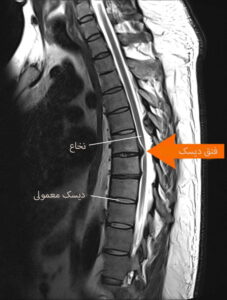

دیسک کمر زمانی رخ میدهد که دیسکهای بین مهرهای تحت فشار بیش از حد قرار گرفته و بیرونزدگی یا پارگی در آن ایجاد شود.